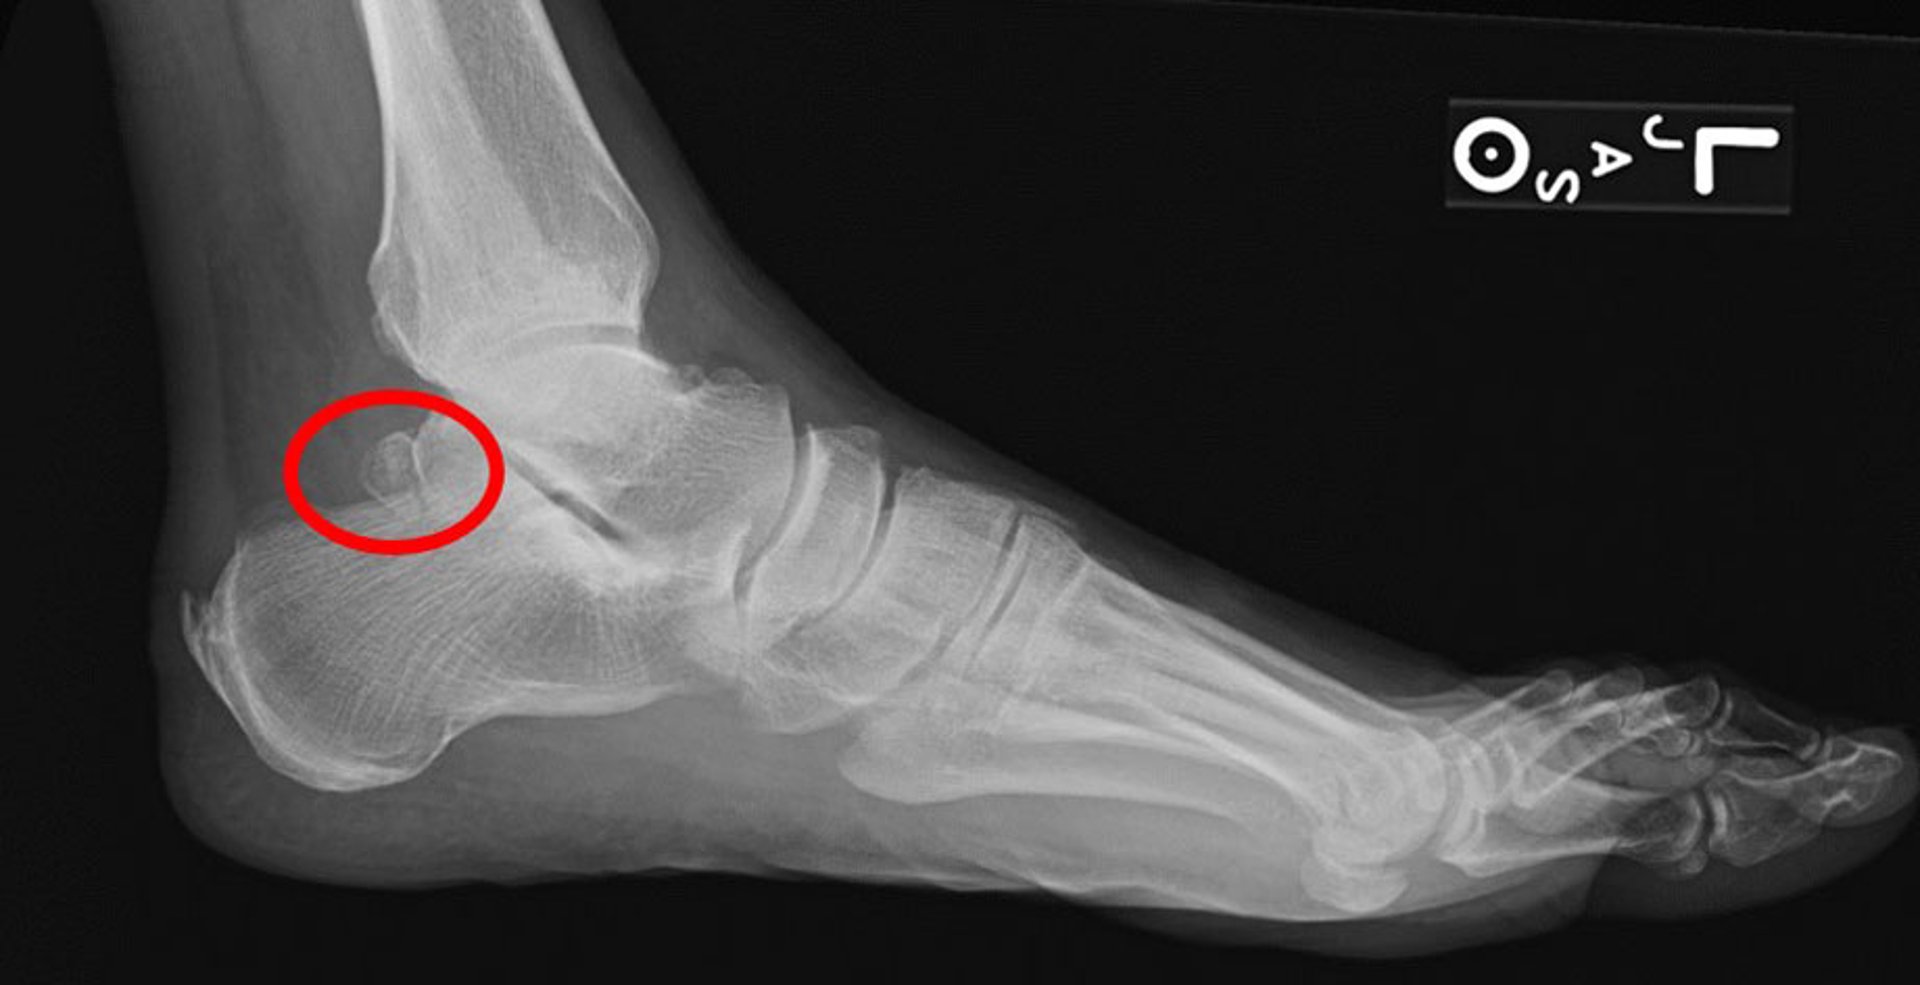

Osso trígono

Esta radiografia lateral mostra um osso trígono (círculo).

Imagem cedida por cortesia de James C. Connors, DPM.